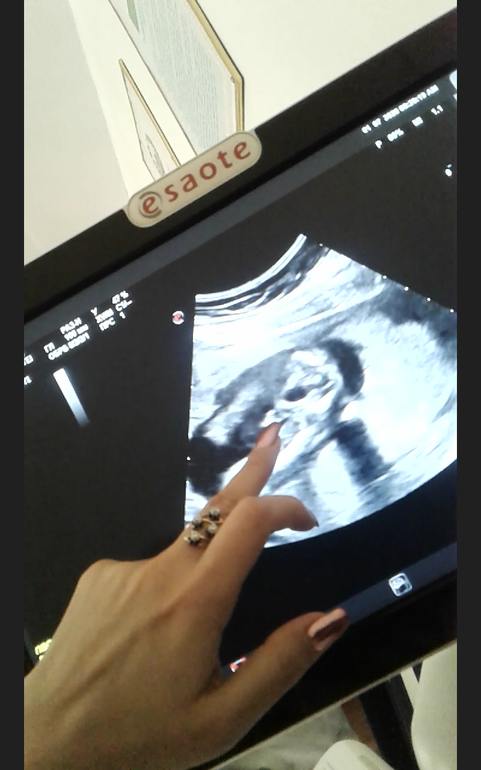

Был 2 скрининг, на 1 нам ничего не сказали по направлению, а сейчас ходили платно делать. Были на узи врач прям с первых секунд сказала нам девочку, моей радости не было предела, что я не рассматривала там ничего между ножек, на вопрос мужа, а точно ли девочка, ответила что еще никто не жаловался, она смотрела и в 3д версии, она хлопала нам в ладошки. Но теперь начитавшись в интернете историй, что узи врет, и рождаются со всем другого пола дети.

В 13 недель предположили мальчика в 19 недель подтвердили и показали достоинство.